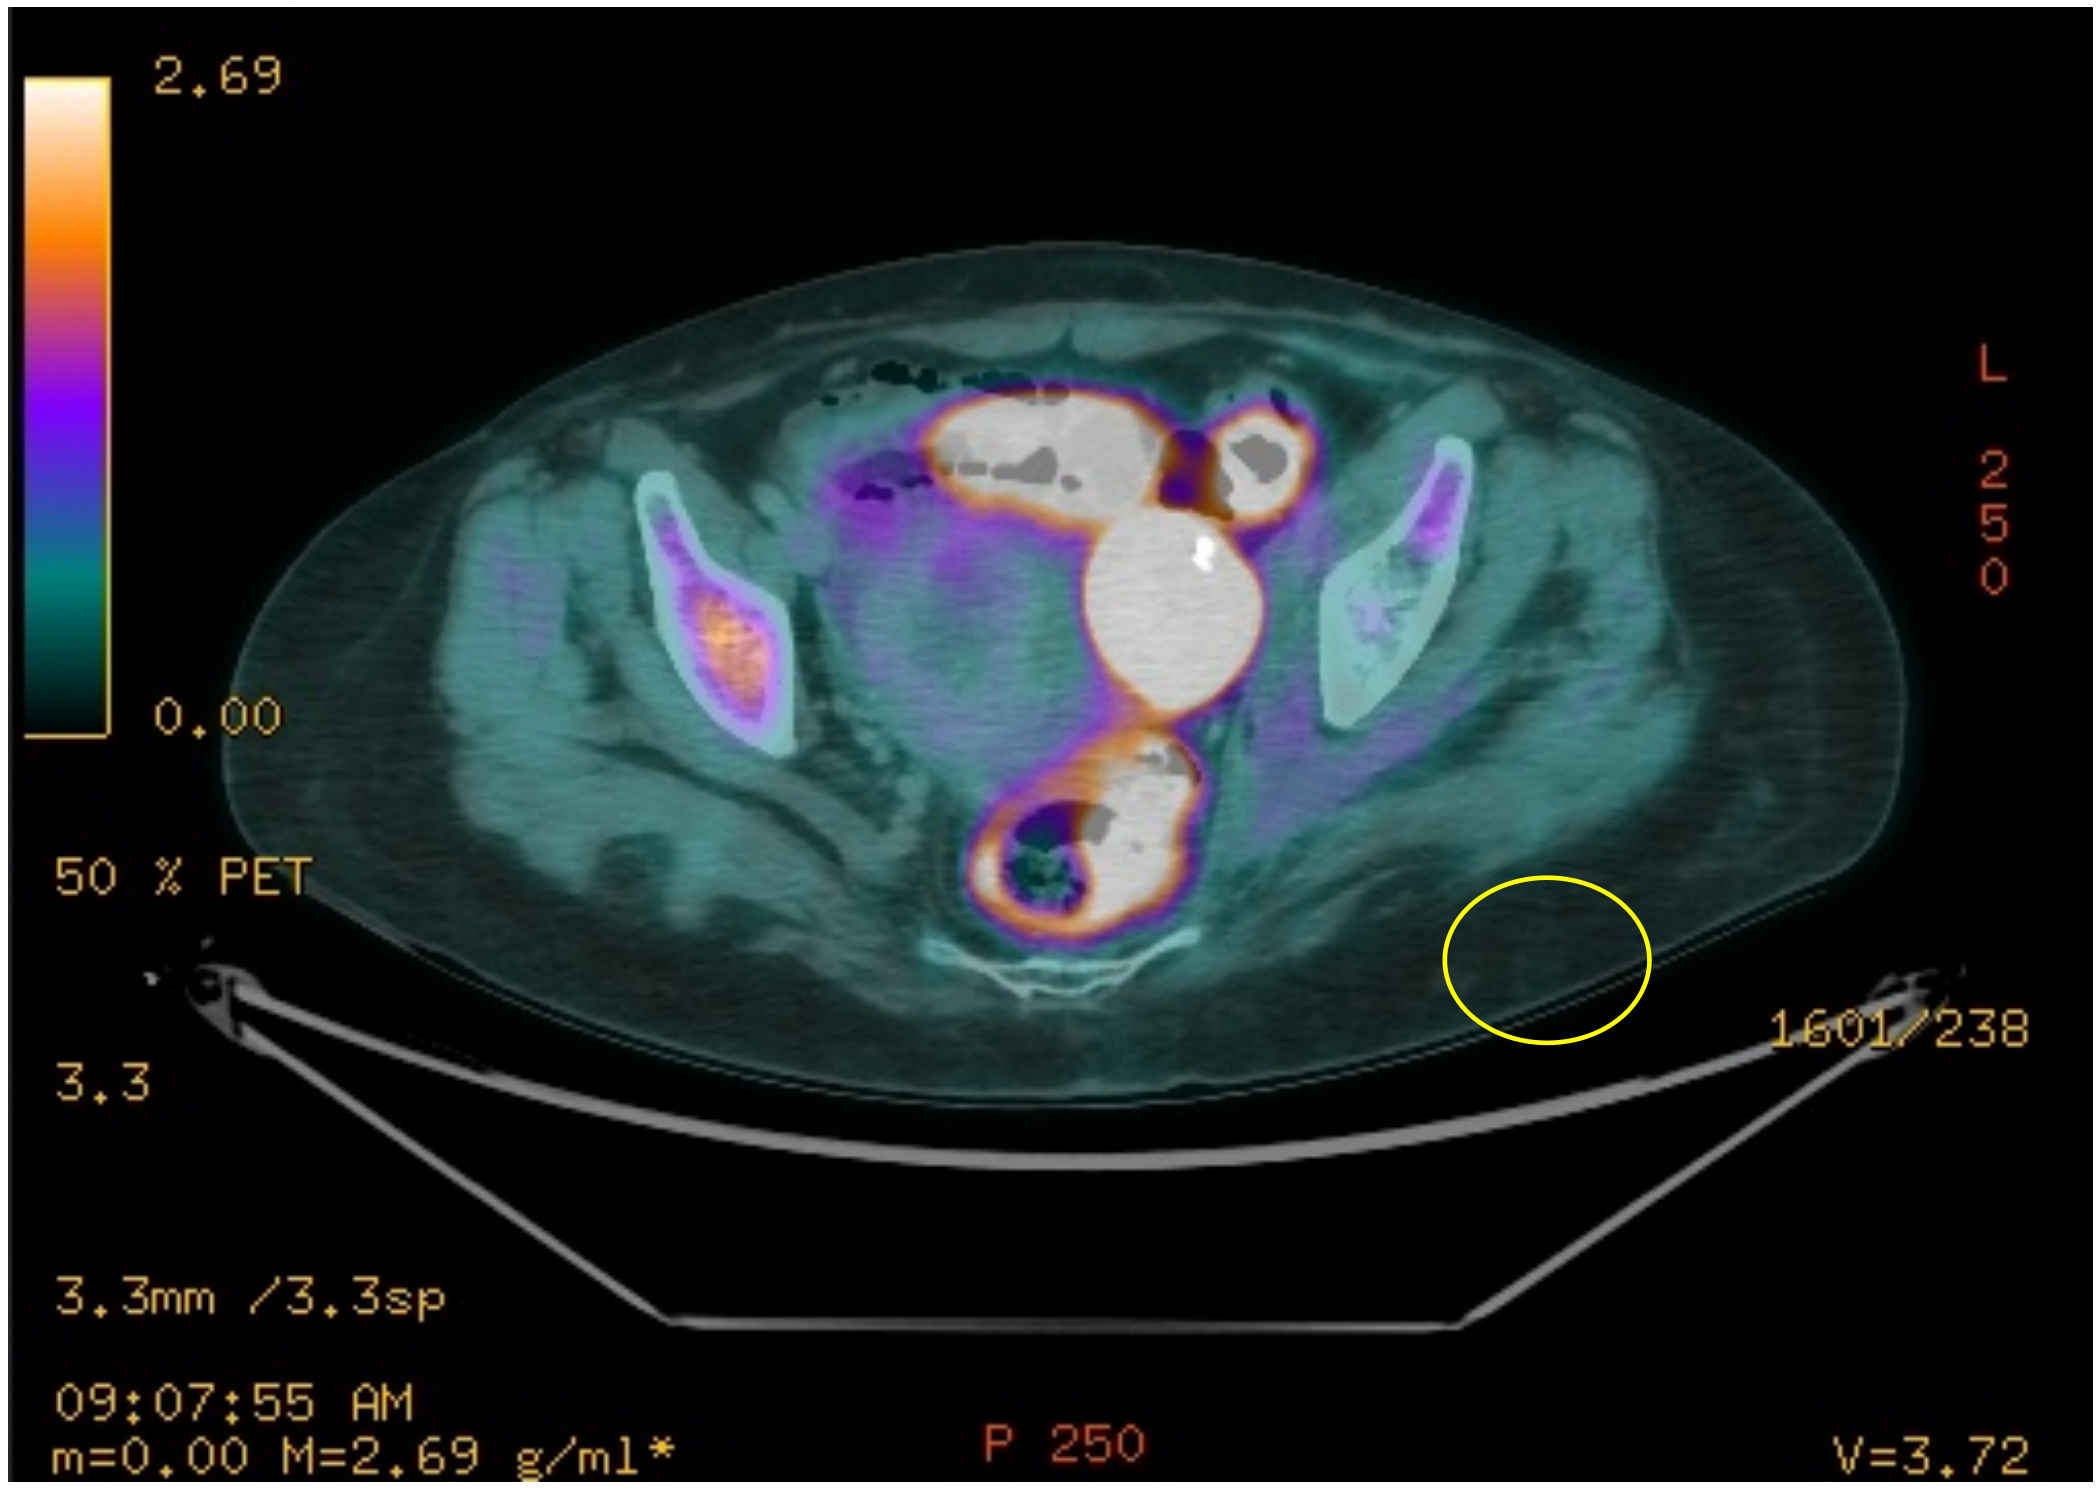

Mujer de 61 años con antecedente de Linfoma difuso de células B grandes.

Se realiza PET/ CT de control en el cual se identifica una lesión con hipermetabolismo en cavidad pélvica de 35 x 45 mm.